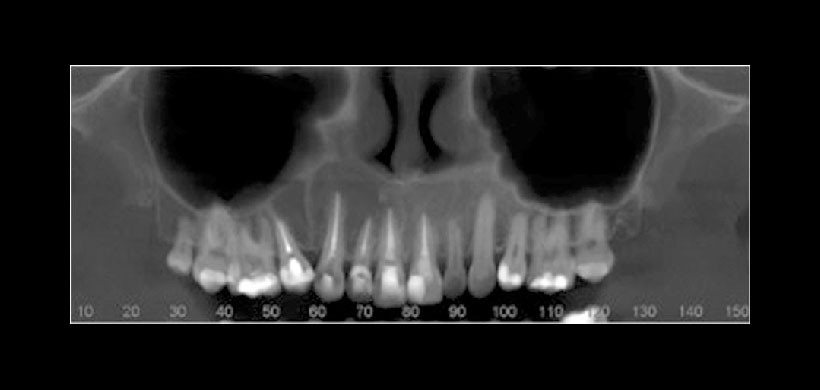

Figura 4: Tomografía cone beam (CBCT). Reformación panorámica que muestra la lesión osteolítica asociada a las piezas mencionadas además se extiende hasta la pieza 1.6.